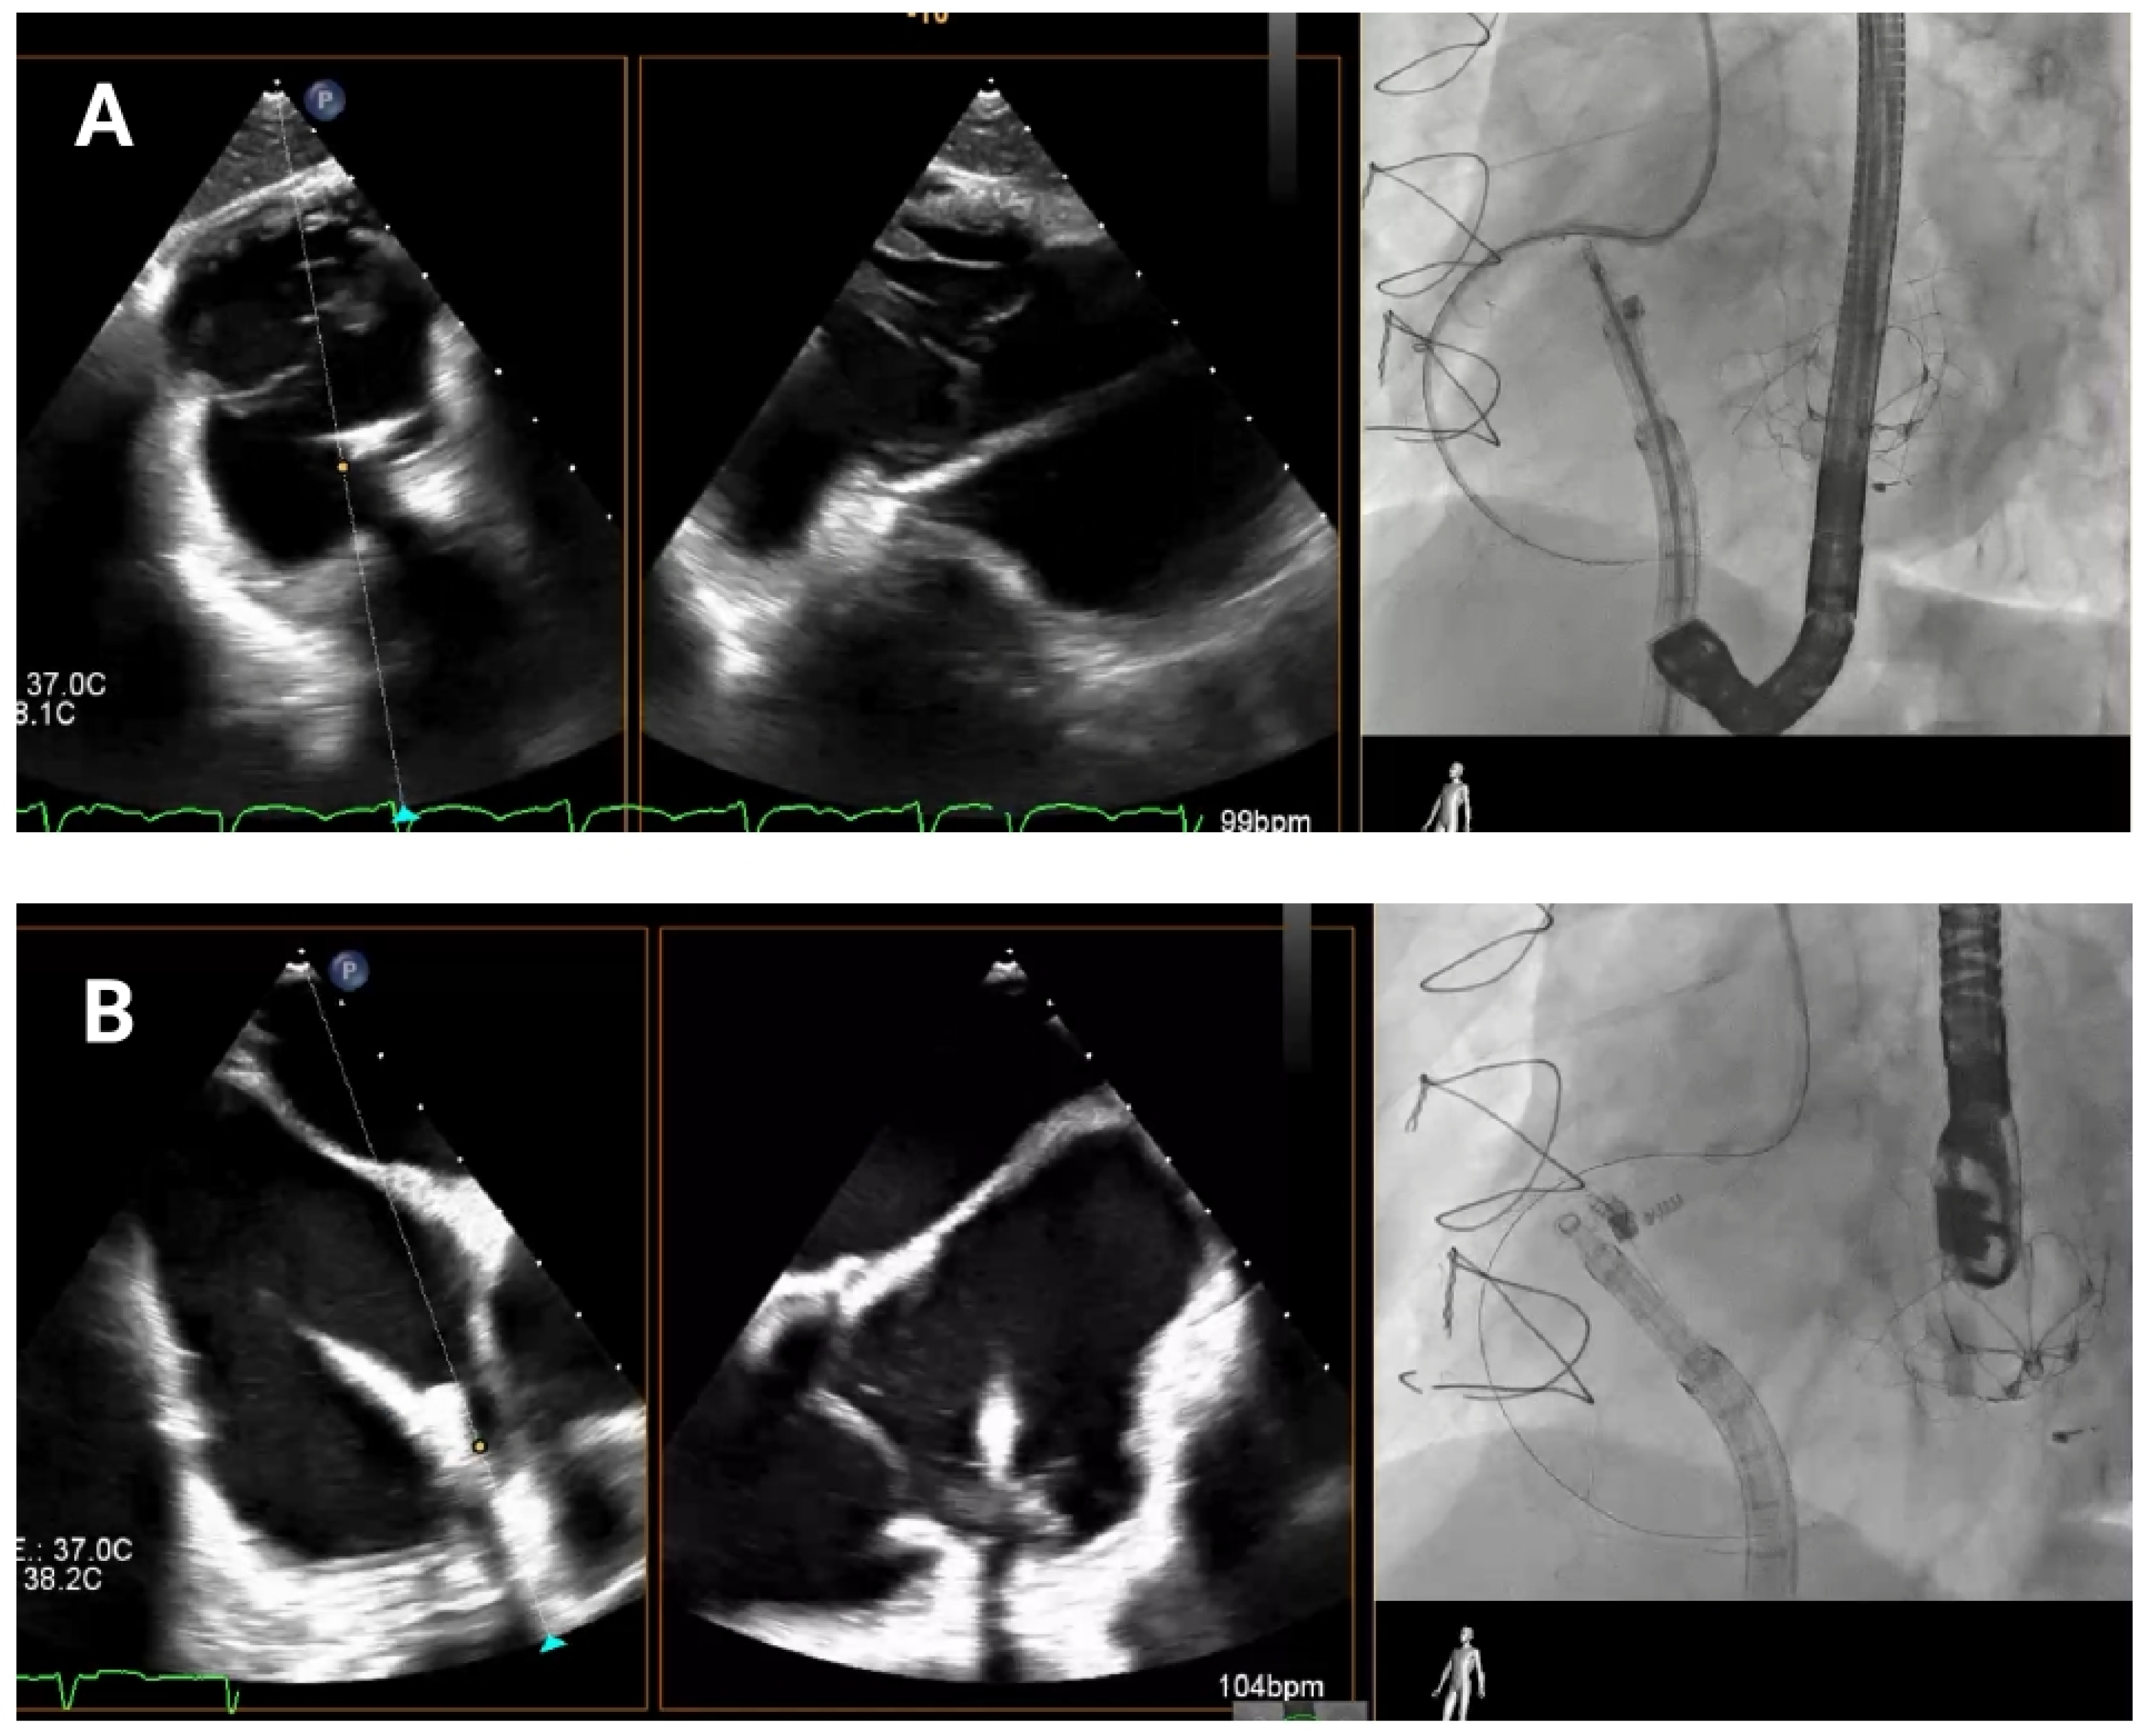

4.4. Band Cinching

In the final release phase of the procedure, the size adjustment tool (SAT) is advanced to contract the Cardioband implant (

Figure 7), a crucial step in securing the device around the tricuspid annulus and effectively reducing the diameter. This reduction is performed in incremental stepwise adjustments, which range between 0 cm and 2.5–3.5–4.5–5.5 cm depending on the chosen band size, to achieve optimal tension and alignment with the annulus. Continuous real-time monitoring with TEE and fluoroscopic imaging is essential during this phase to confirm successful positioning and ensure gradual tightening without impinging on surrounding structures or compromising valve function.

Figure 7.

Band cinching and post-implant assessment. The size adjustment tool is used to cinch the Cardioband, reducing the tricuspid annular diameter by 3.5–5.5 cm depending on the band size. Pre-cinching (A) and final result post-cinching (B).